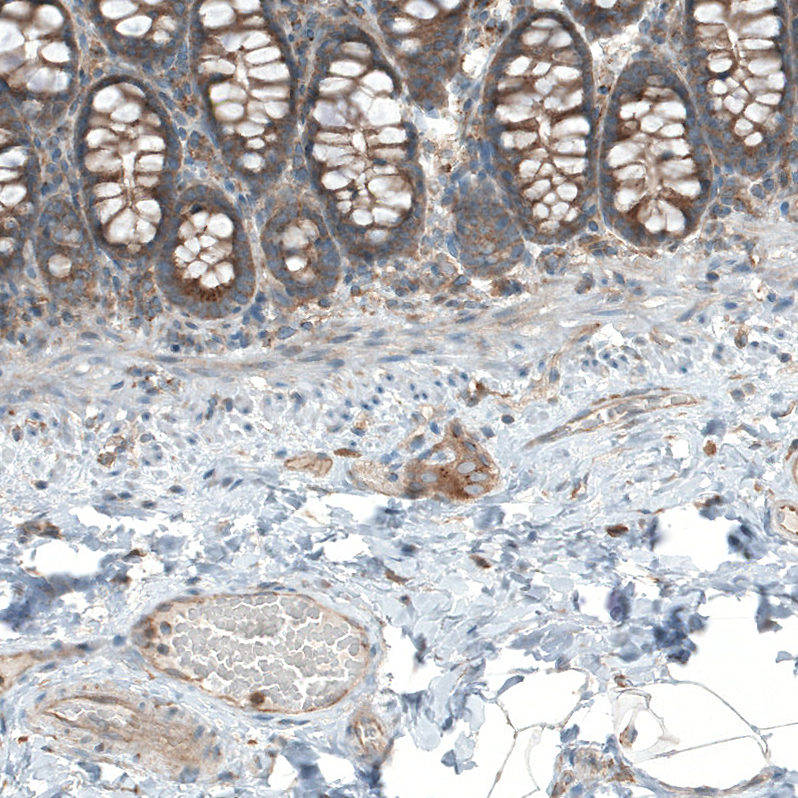

Immunohistochemical staining of human rectum shows moderate granular cytoplasmic positivity in peripheral nerve / ganglion and glandular cells.